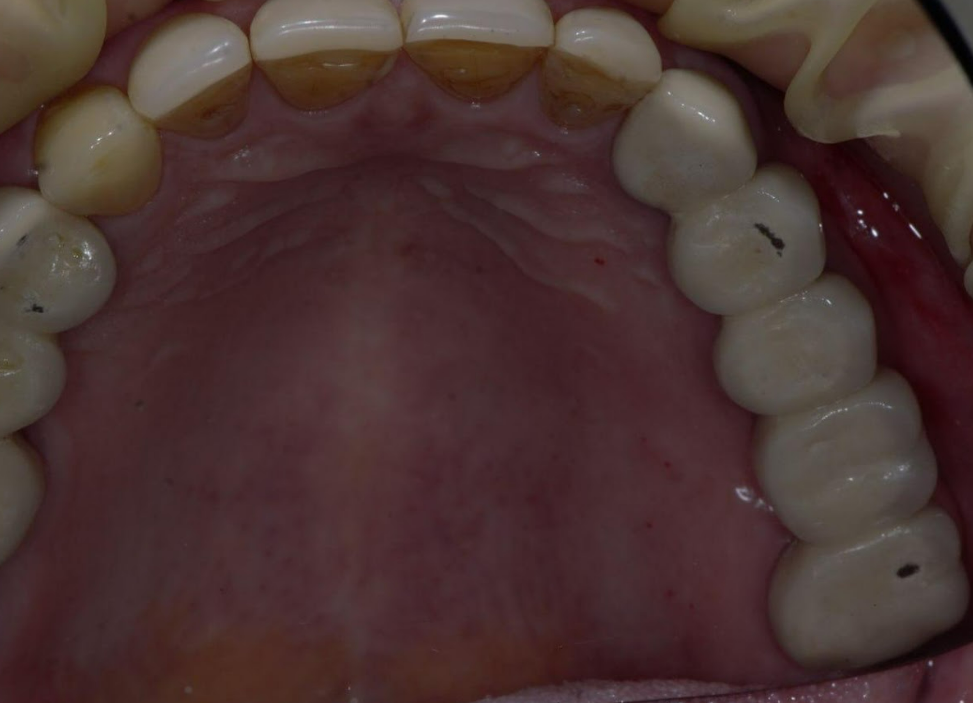

The screw-retained zirconia bridge and the crowns on teeth 13 and 17 show a precise fit, as seen in the photo below.

The completed restoration, with sealed screw access holes, is aesthetically pleasing and anatomically correct. Masticatory function is fully restored, and the patient is completely satisfied with the result.

The gingival contour around the prosthesis is well-defined; the papillae completely fill the embrasures, and a band of attached keratinized gingiva is clearly visualized and anatomically correct.